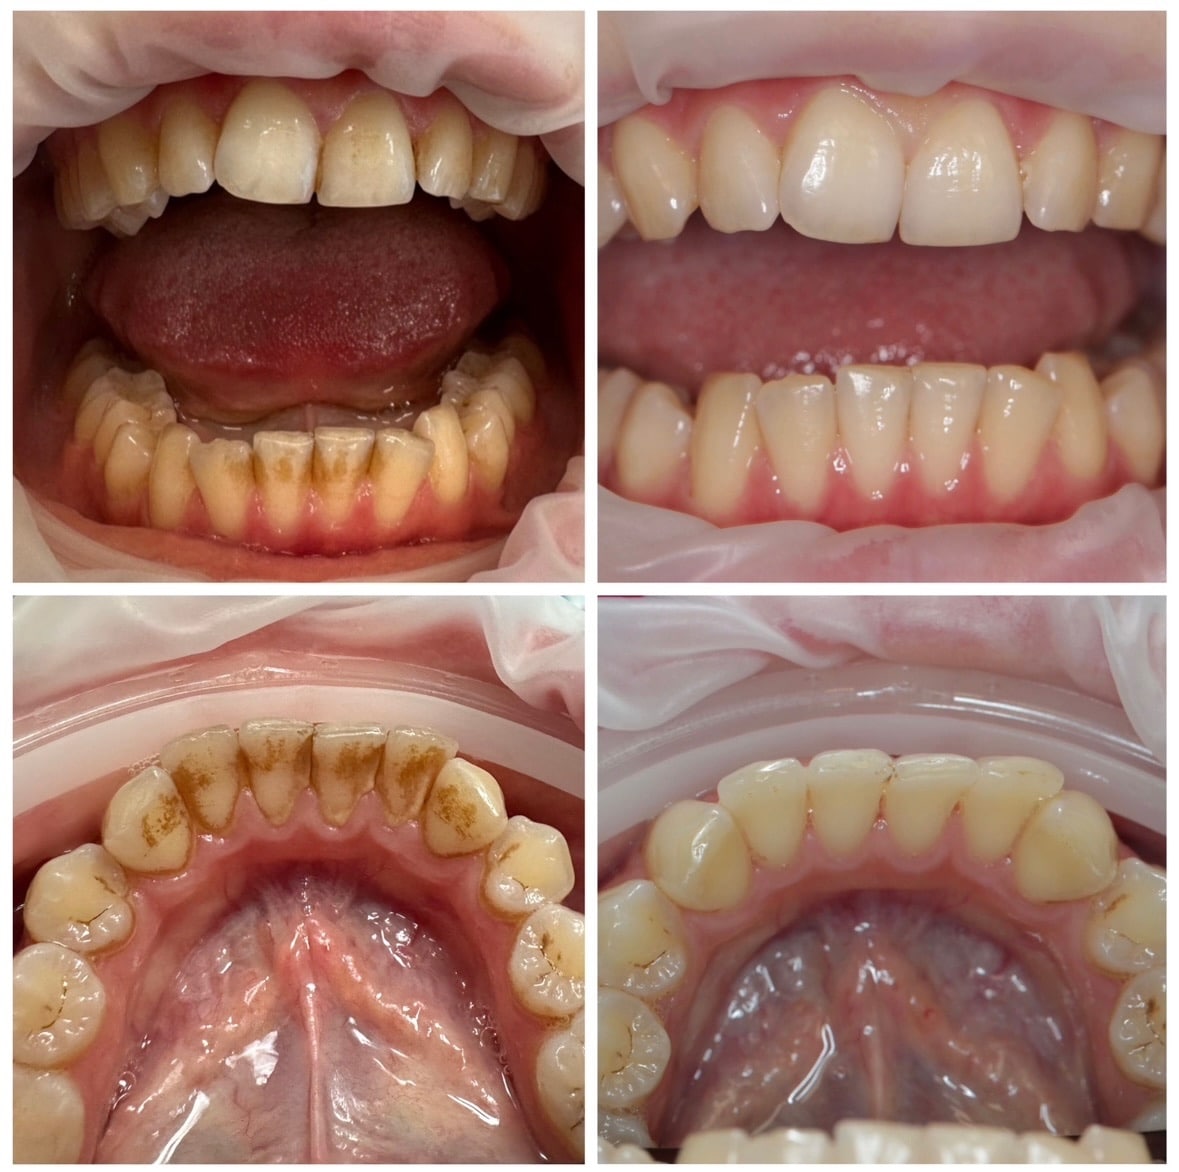

Esteetiline hambaravi, restauratiivne hambaravi, suukirurgia